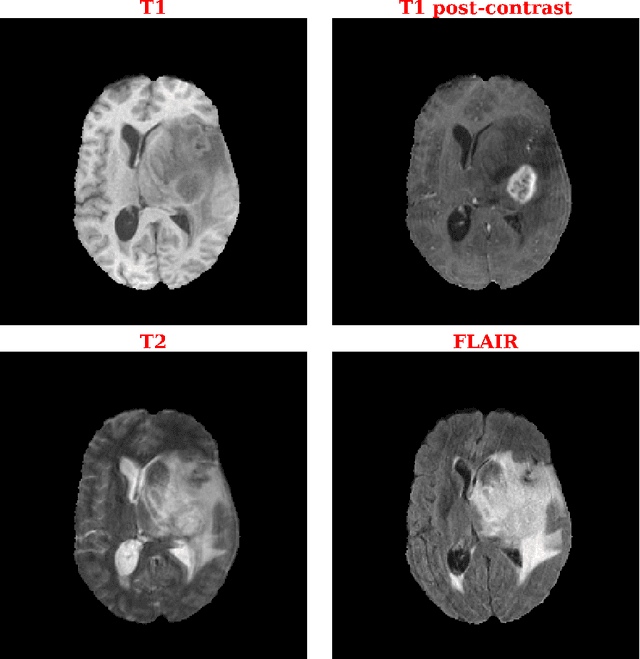

Abstract:Purpose: Deep Neuroevolution (DNE) holds the promise of providing radiology artificial intelligence (AI) that performs well with small neural networks and small training sets. We seek to realize this potential via a proof-of-principle application to MRI brain sequence classification. Methods: We analyzed a training set of 20 patients, each with four sequences/weightings: T1, T1 post-contrast, T2, and T2-FLAIR. We trained the parameters of a relatively small convolutional neural network (CNN) as follows: First, we randomly mutated the CNN weights. We then measured the CNN training set accuracy, using the latter as the fitness evaluation metric. The fittest child CNNs were identified. We incorporated their mutations into the parent CNN. This selectively mutated parent became the next generation's parent CNN. We repeated this process for approximately 50,000 generations. Results: DNE achieved monotonic convergence to 100% training set accuracy. DNE also converged monotonically to 100% testing set accuracy. Conclusions: DNE can achieve perfect accuracy with small training sets and small CNNs. Particularly when combined with Deep Reinforcement Learning, DNE may provide a path forward in the quest to make radiology AI more human-like in its ability to learn. DNE may very well turn out to be a key component of the much-anticipated meta-learning regime of radiology AI algorithms that can adapt to new tasks and new image types, similar to human radiologists.